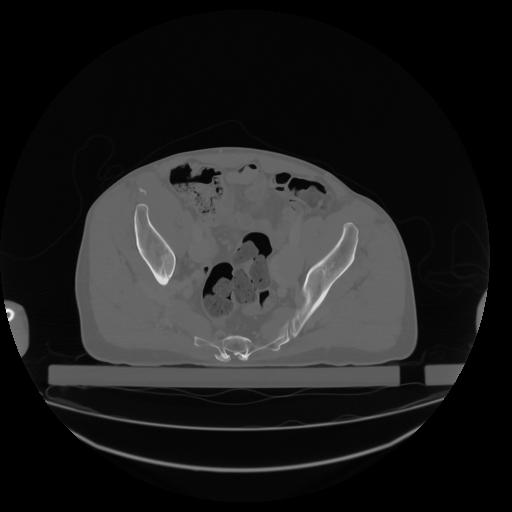

27 CUERPO,CE,Axial,3.0,CUERPO,,